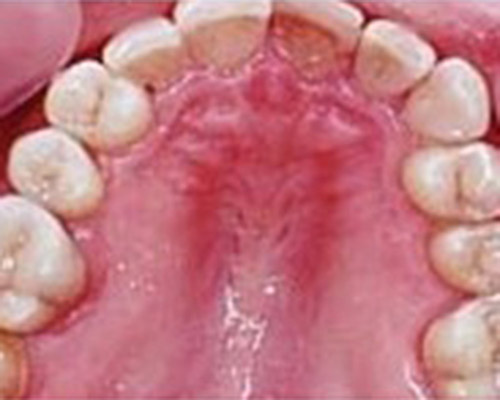

Gentle and painless treatment of dental caries and dental lesions using the most modern techniques and materials from renowned companies with emphasis on aesthetics and functional tooth restoration.

We produce photocomposite, ceramic (inlay, onlay) and amalgam fillings of the latest generations.